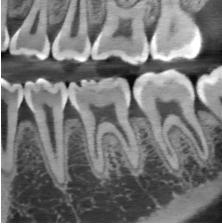

Posición I: cuando la mayor parte de la corona, se encuentra a nivel del tercio cervical de la raíz de los dientes adyacentes.

Posición II: cuando la mayor parte de la corona, se encuentra a nivel del tercio medio de la raíz de los dientes adyacentes.

Posición III: cuando la mayor parte de la corona, se encuentra a nivel del tercio apical de las raíces de los dientes adyacentes.

Power y Short afirman en su análisis, que si el ángulo resultante formado entre la línea vertical determinada por la espina nasal anterior y el eje longitudinal del canino sea mayor a 31°, el éxito del acomodo del canino en el arco dental es reservado (Camarena-Fonseca et al. ,2017) (Figura 19).

2. Si la angulación aumenta, el riesgo de impactación del canino sobre el diente lateral, incrementará el riesgo de reabsorción radicular del diente lateral en un 50%, así como una franca inclusión (Figura 22).